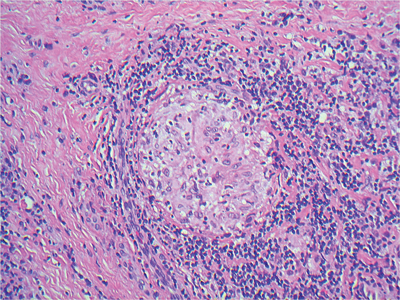

A 45-year-old man presents with left-sided epiphora. During a dacrocystorhinostomy (DCR), the wall of the lacrimal sac was noted to be bulky. The sac wall is biopsied and sent for routine histopathology examination. The pathologist notes a distinctive feature in the wall of the lacrimal sac biopsy, shown in Figures 1 and 2.

Figure 1.

1. Haematoxylin and eosin.

2. These are epithelioid histiocytes.

3. This is a granuloma and this is granulomatous inflammation.

4. Foreign body, infection (fungal and mycobacterial), sarcoidosis are the main differentials.

5. The patient had no infectious agents on the histology and microbiology grew no organisms. The likeliest diagnosis is sarcoidosis of the lacrimal sac.